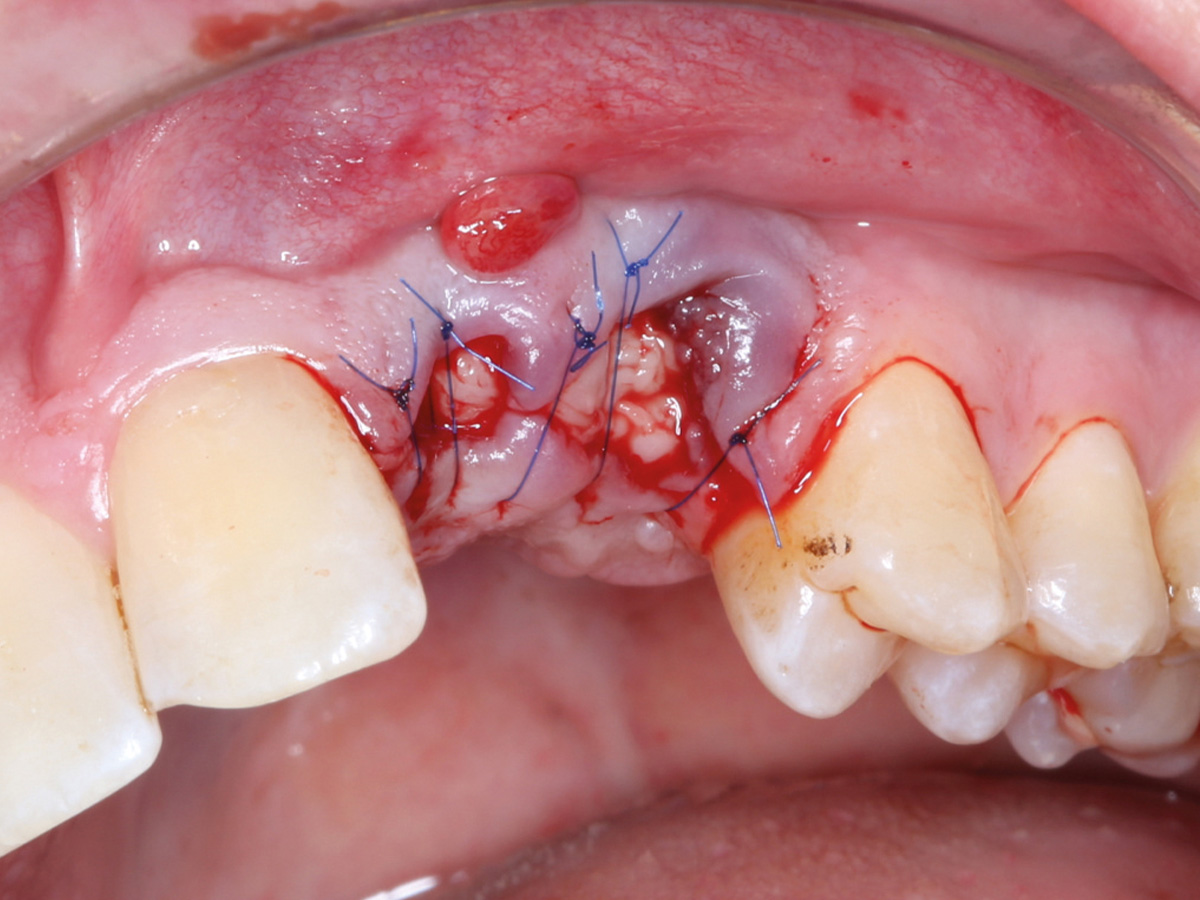

Abbildung 1

Klinische Ausgangssituation lateral, spontane Blutung.

Abbildung 15

Nach mikrochirurgischem Nahtverschluss.

Therapie

Nach Extraktion der Zähne 22 und 23 wurden die Alveolen mit PRGF Endoret (BTI) aufgefüllt. Auf eine achtwöchige Ausheilungsphase folgten Reentry und Wiederherstellung des Alveolarfortsatzes mit Hilfe der Double-Layer-Technik modifiziert mit PRGF Endoret. Nach sechsmonatiger Ausheilungsphase erfolgte eine Implantation in regio 22 und 23, die anschließend mit einer provisorischen Versorgung verschraubt wurde. Der Zahnersatz wird nach Ausheilung der Weichgewebe abschließend eingesetzt.